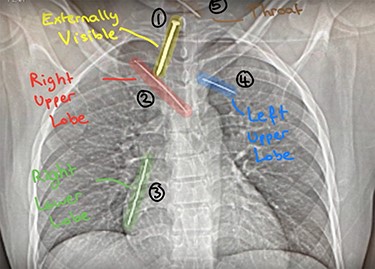

This is a report of a 31-year-old male refugee with a history of psychiatric problems, who was admitted to the Intensive Therapy Unit after being found on a motorway. He was in severe chest pain after escaping extreme torture from his home country. On examination, he found to have a nail (Nail 1) penetrating the anterior chest wall (Fig. 1). On further imaging (Fig. 2), he had three further nails in his thorax (Nail 2: right upper lobe, Nail 3: right lower lobe, Nail 4: left upper lobe).

Chest X-ray: detailing the position of four nails within the thorax (Nail 2: right upper lobe; Nail 3: right lower lobe; Nail 4: left upper lobe) and Nail 5 (throat).